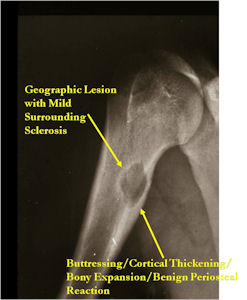

Plain X-rays:

- Geographic, circumscribed lesion usually around 5cm in size.

- There may be expansion of bone, cortical thinning and cortical breakthrough. A soft tissue mass may accompany this lesion but the soft tissue component is usually contained by the periosteum.

- The periosteum remains intact around the soft tissue component. Might need a CT scan to detect the subtle calcification (Egg Shell Rim of Calcification) associated with an intact periosteal reaction

- The lesion may be entirely radiolucent but usually shows some degree of mineralization. Mineralization may appear stippled like cartilage but do not see chondroid pathologically. Mineralization is sometimes better detected on a CT scan rather than an x-ray.

- Usually less surrounding sclerosis than an osteoid osteoma.

- Arise from the Diaphysis (75%) more commonly than Metaphyseal (25%)

- 4 cm to 6 cm in size